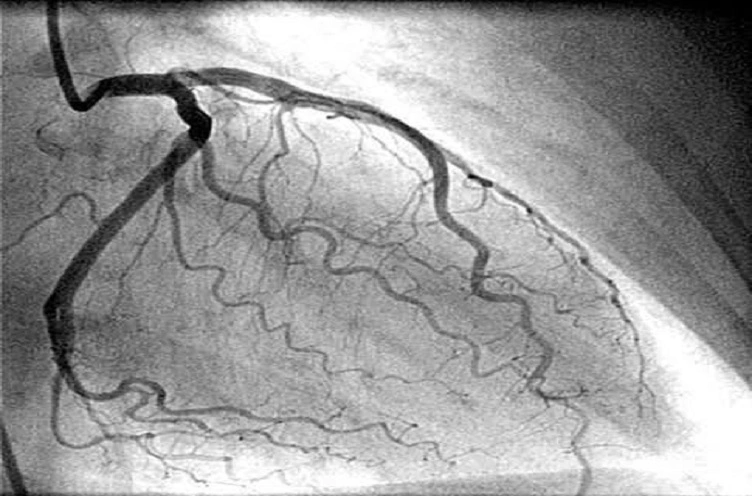

Una angioplastia coronaria es un procedimiento para abrir arterias coronarias estrechas o bloqueadas. El Dr. Sergio Alberto Rodríguez López la realiza para mejorar el flujo sanguíneo en el corazón y se recomienda en casos de enfermedad coronaria significativa.